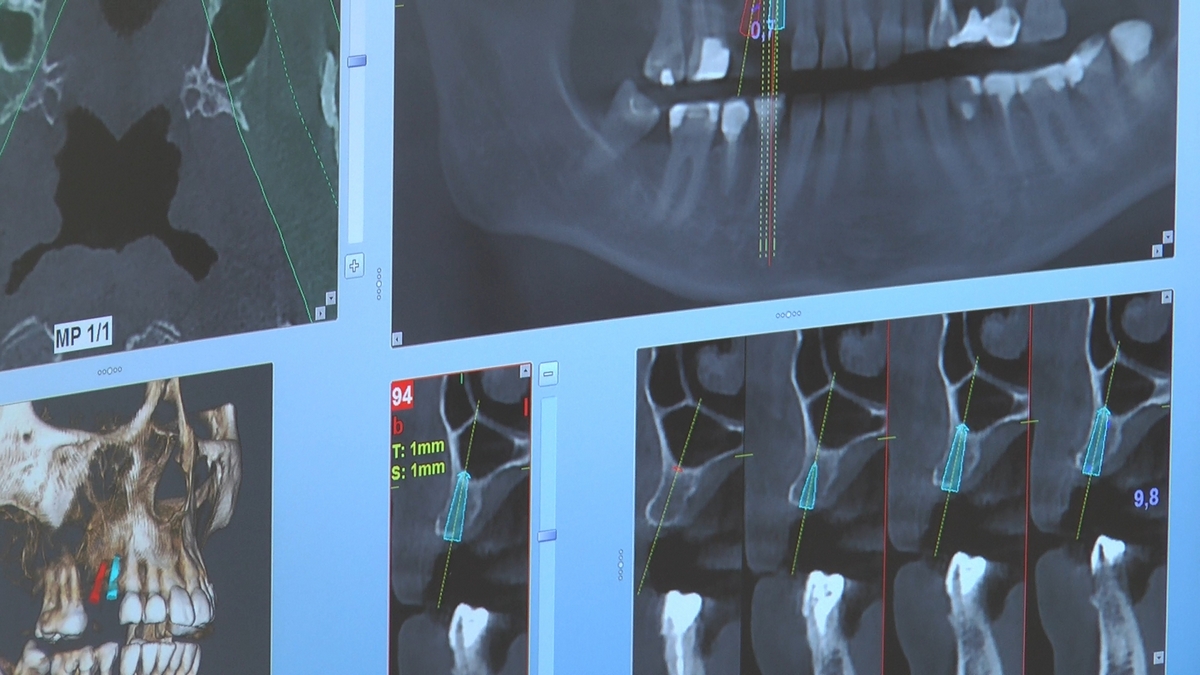

W trakcje dwóch dni zabiegowych, piątek i sobota, 5 i 6 października 2018 roku, lekarze uczestniczący w 6 Sesji VI Sezonu, wykonali wiele zabiegów o wysokim stopniu trudności. Przeprowadzili je pod kierunkiem Mentorów Instytutu Vivadental – dr n.med. Violetty Szycik, dr n.med. Magdaleny Kisłowskiej-Syryczyńskiej oraz dr Małgorzaty Piotrowskiej.

Wprowadziliśmy łącznie 25 implantów w tym wykonaliśmy:

dwa zabiegi All- on -4 / jeden w szczęce, jeden w żuchwie/ z usunięciem zębów i natychmiastową implantacją oraz natychmiastową odbudową protetyczną

jeden zabieg sinus lift otwarty